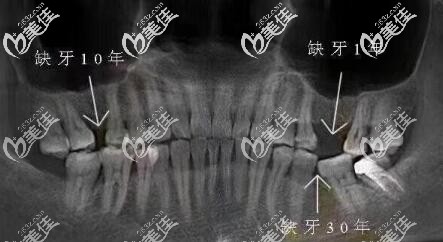

牙齒缺失10多年,旁邊牙齒傾斜還能做種植牙修復嗎?

牙齒缺失要及時鑲牙、種牙,如果不及時種牙,旁邊其它的牙齒會向缺牙方向逐漸傾斜,對面牙齒逐漸伸長。容易食物嵌塞,引起牙周問題,從而導致更多健康牙齒發(fā)生問題。

缺牙10多年,想要種植牙修復,此時缺牙部位可能上下和左右間隙都不夠,此情況是可以考慮牙齒矯正關閉間隙,或者先正畸,拉開間隙,再做種植牙,具體情況還需要拍牙片。

牙齒缺失不盡快修復,無特殊情況一般半年以后就開始傾斜,隨著時間越長傾斜越厲害,鄰牙傾斜是個慢化過程,正常情況下個人很難感應到,有些人會有輕微的面部變化。